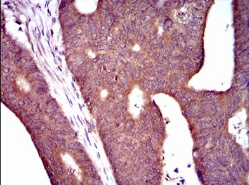

IHC    1/200 - 1/1000